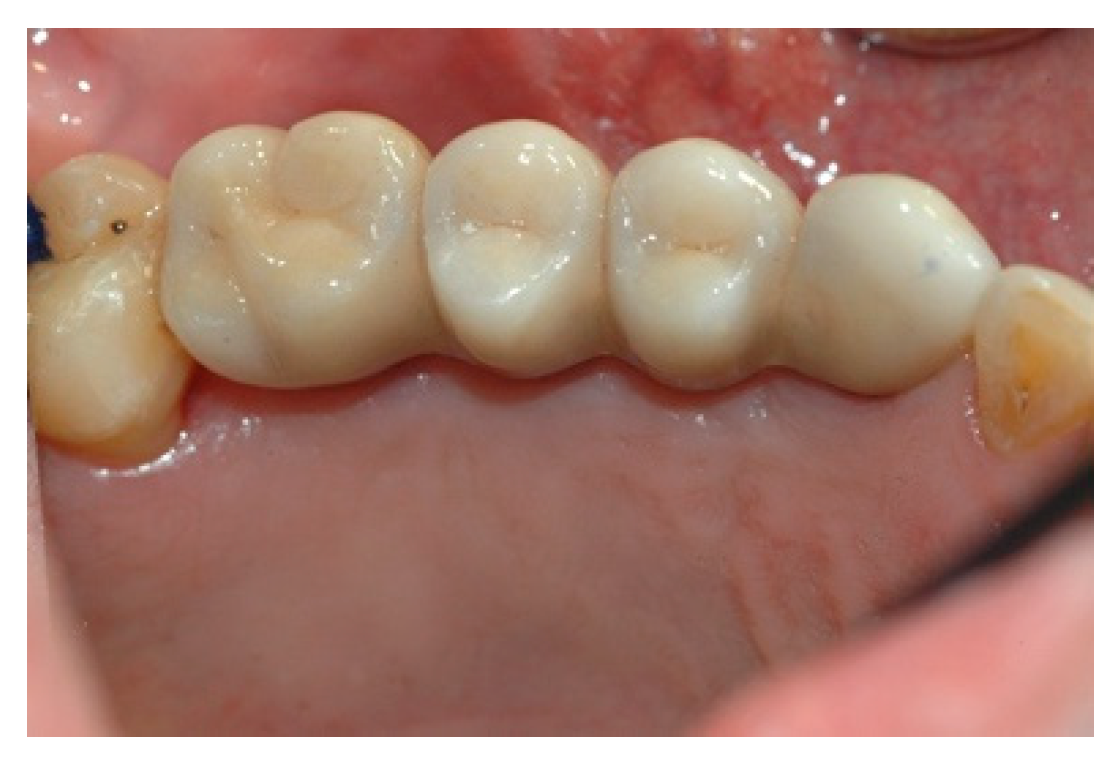

Once the mesostructure was made, it was checked to verify passive adaptation and its precise coupling with the arched fixtures (Figure 8 and Figure 9).

Upon positive feedback, the construction of a superstructure was carried out by performing fusion and subsequent ceramicization in the laboratory (Figure 10 and Figure 11).

Figure 8. Mesostructure test.

Prosthesis 02 00023 g008

Figure 9. Mesostructure test.